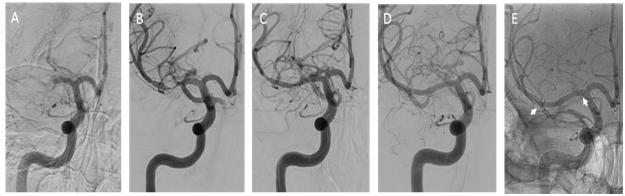

A 36-year-old Caucasian woman presented to the Emergency Department after she was found down on floor, at her home. She had a history of bipolar disorder, no head trauma or vascular risk factors. She was last seen normal about six hours prior to her arrival to the hospital. Upon neurological examination, she was noted to have dense left hemiparesis, forced right gaze deviation and severe dysarthria, the National Institutes of Health Stroke Scale (NIHSS) was 10. A computerized tomography of the head demonstrated a hyperdense right middle cerebral artery (MCA) and no other obvious hyperdensities associated. An emergent magnetic resonance imaging (MRI) of the brain was performed (Figure 1). The MRI of the brain demonstrated early ischemic changes in the right hemisphere, less than one third of the right middle cerebral artery vascular territory, the MRI angiography showed an occlusion of the right M1 segment and an intramural hematoma was also noted in the right M1 segment. Knowing this information, the patient was emergently taken to the angio suite and the diagnosis was made of right M1 occlusion due to an intracranial dissection (Figures 2A–2C).

Figure 2 Digital subtraction imaging. (A) Anterior posterior view contrast angiogram demonstrating occlusion of the right M1 segment. (B) Double angiogram demonstrating the disrupted vessel. (C) Angiogram showing stent placement. (D) Follow up at 6 months. (E) Unsubtracted angiography demonstrating the stent at six months (arrows).

A 0.014-inch Synchro-2 standard microwire (Stryker Corporation, Kalamazoo, Michigan, USA) was used to reach (was advanced towards) the lesion and a Prowler Select Plus microcatheter (Codman, Raynham, Massachusetts, USA) was advanced over this guide wire. The wire was then removed and a double angiogram (via simultaneous microcatheter and guide catheter injection) demonstrated the area of stenosis/occlusion. An Enterprise 4.5x22mm (Codman, Raynham, MA) stent was then placed across the area of stenosis/occlusion. The patient was given an intravenous load of Integrilin (Eptifibatide) 135mcg/Kg and was loaded orally with aspirin 325mg and clopidogrel 300mg, to follow with daily aspirin 81mg and clopidogrel 75mg.

Clinically the patient improved on the table and was able to raise the left hemibody against gravity (MRC grading for muscle strength=4), we noticed complete resolution of the gaze deviation and improved dysarthria. A follow up CT head was performed on the day 1 (Figure 3). The patient was discharged home with outpatient rehabilitation and NIHSS=2.

At three months, the patient had returned to her baseline with a modified Rankin score (mRS) of 0 and NIHSS of 0. Despite the lack of symptoms, the dual antiplatelet therapy was continued for about 6 months, time when she had a follow up angiogram (Figure 2D&2E).